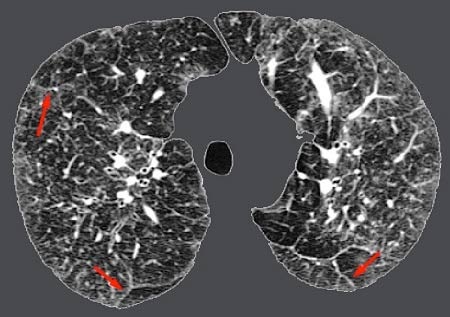

Trên phim chụp Xquang, chụp cắt lớp vi tính, có thể thấy hình ảnh tổn thương của phổi. Nội soi phế quản thấy tổn thương giúp ích cho chẩn đoán bệnh. Trong xét nghiệm chức năng phổi (PFTs) hoặc cho bệnh nhân tập thể dục thử nghiệm sẽ thấy các triệu chứng của bệnh phổi kẽ nặng lên khi hoạt động. Từ đó bác sĩ có thể đánh giá chức năng phổi.